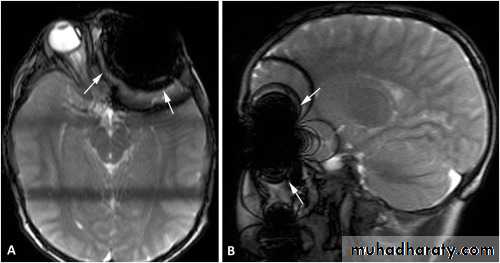

Imaging: the selection of the imaging modality to detect a foreign body should depend on its position, composition and size.

Imaging modalities used are as follows:1. Conventional radiography: it is a noninvasive, inexpensive modality;multiple views are needed (at least 2 views: anteroposterior andlateral).2. Computed tomographic (CT) scan: it has a very important role invisualizing and locating foreign bodies, even radiolucent ones; it alsoprovides information about local anatomy, tissue reaction, and abscess formation.

3. Fluoroscopy: C-arm imaging equipment allows for real timeradiographic visualization of the foreign body.4. Magnetic resonance imaging: it is used in nonmetallic foreign bodies; it provides detailed information regarding tissue reaction.5. Ultrasonography.